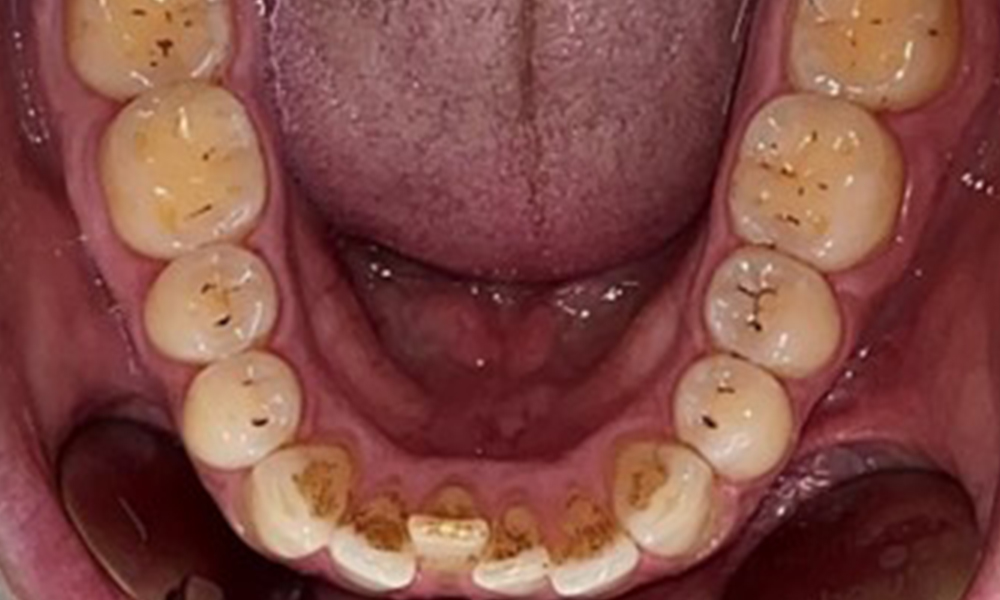

The patient has full dentition with a total of 28 teeth. There were noteworthy erosions and attritions. (Fig. 4, Fig. 5). Due to bruxism, the patient has been wearing a splint with an adjusted bite block at night for many years. The erosions were caused by long-term consumption of isotonic beverages. No periodontal bone loss or active caries were observed.

Instruction and motivation are important components of these appointments. Good home-based intraoral hygiene behaviour and understanding are important for patients. Plaque accumulation is particularly evident in the cervical regions (Fig. 8).